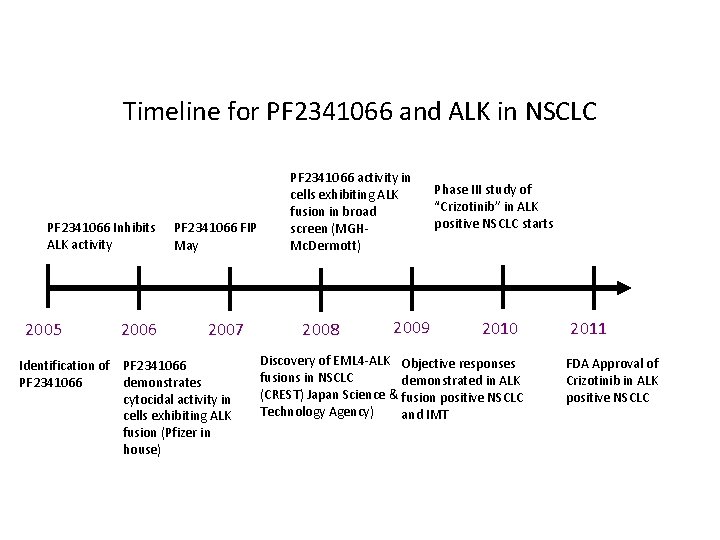

Timeline for PF 2341066 and ALK in NSCLC PF 2341066 Inhibits ALK activity 2005 2006 PF 2341066 FIP May 2007 Identification of PF 2341066 demonstrates cytocidal activity in cells exhibiting ALK fusion (Pfizer in house) PF 2341066 activity in cells exhibiting ALK fusion in broad screen (MGHMc. Dermott) 2008 2009 Phase III study of “Crizotinib” in ALK positive NSCLC starts 2010 Discovery of EML 4 -ALK Objective responses fusions in NSCLC demonstrated in ALK (CREST) Japan Science & fusion positive NSCLC Technology Agency) and IMT 2011 FDA Approval of Crizotinib in ALK positive NSCLC